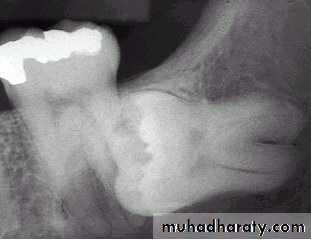

1- clinical inspection to disclose the missing tooth2- radiographic assessment showing the position of the unerupted tooth

3- standard radiographic technique used to localize the unerupted tooth and these will include

b – periapical and occlusal filmc – panoramic view (OPG)

Relation of the impacted maxillary third molar to the maxillary sinus

Class A sinus approximation ( less than 2 mm bone between the antrum and the impacted tooth )Class B non sinus approximation ( more than 2 mm of bone exist between the impacted tooth and the sinus )